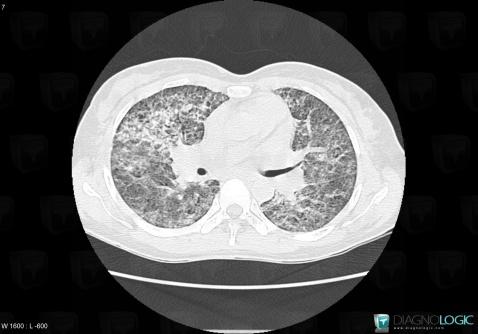

Pneumocystosis, Pulmonary parenchyma, CT

Here is the specific information in the key image above:

- Diagnosis Pneumocystosis, Location(s) Pulmonary parenchyma, with gamuts Acute consolidation, Disseminated consolidation